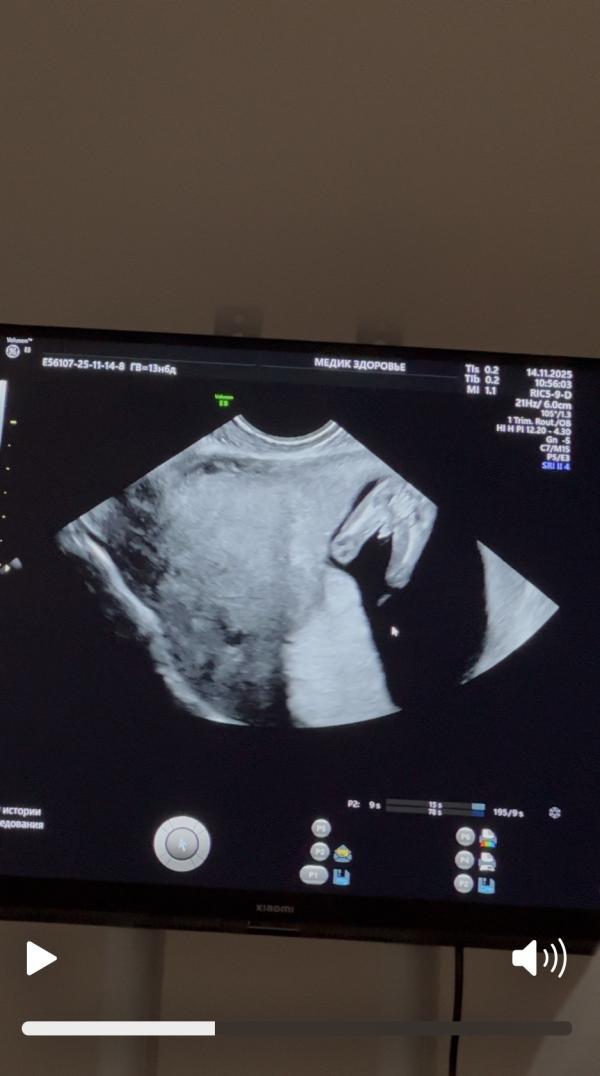

Первое фото сделано вчера, вторые 2 сегодня. Как думаете мальчик или девочка?)

Разный пол сказали на двух УЗИ😄

Вчера мне с уверенностью без «похоже» дали конверт с полом. Сегодня узистка сказала , что на первом скрининге конвертов не дает и сказала , что похоже на девочку, потом , что похоже и на мальчика и на девочку.